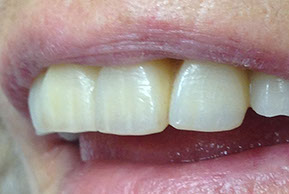

faccette estetiche

agenesia di un incisivo laterale